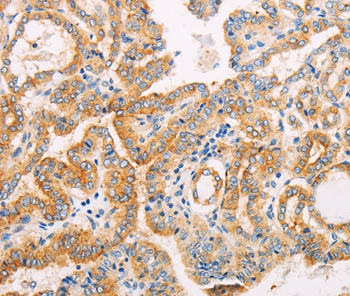

分类: 科研抗体货号: P42786别名: CIS3; SSI3; ATOD4; Cish3; SSI-3; SOCS-3应用: WB,IHC反应种属: Human,Mouse